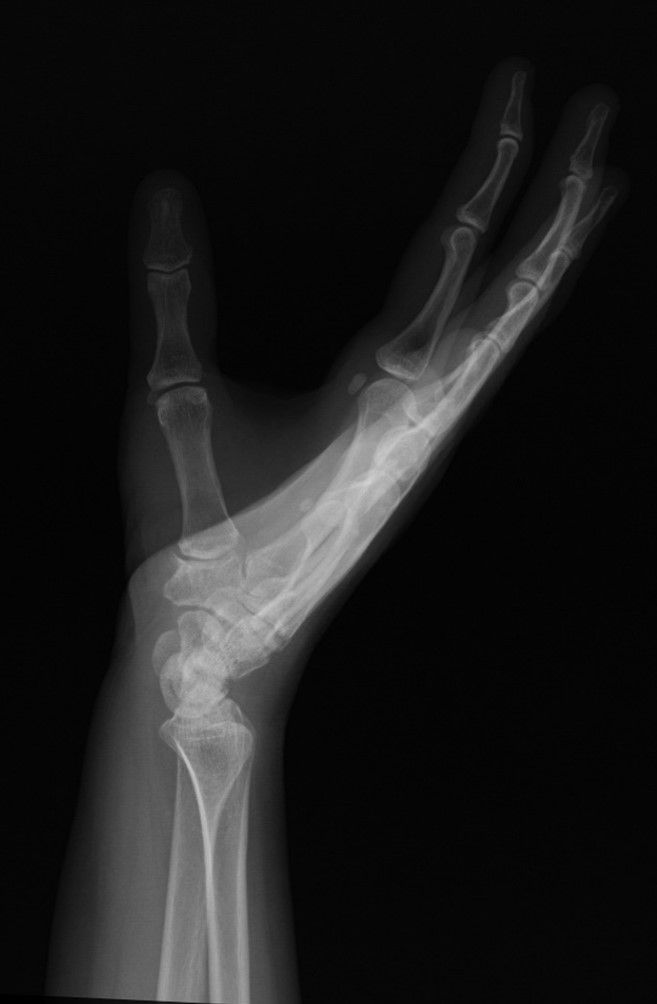

Case 17 - 1.CMC Arthritis (İnterposition Arthroplasty)

45 yr, female, housewife, right hand dominant

Pain felt at left hand 1st CMC joint while grasping for 2 years

Mild pain relief after thumb spica splint, NSAIDs and corticosteroid injection

Crepitation felt with the movement of 1st CMC joint